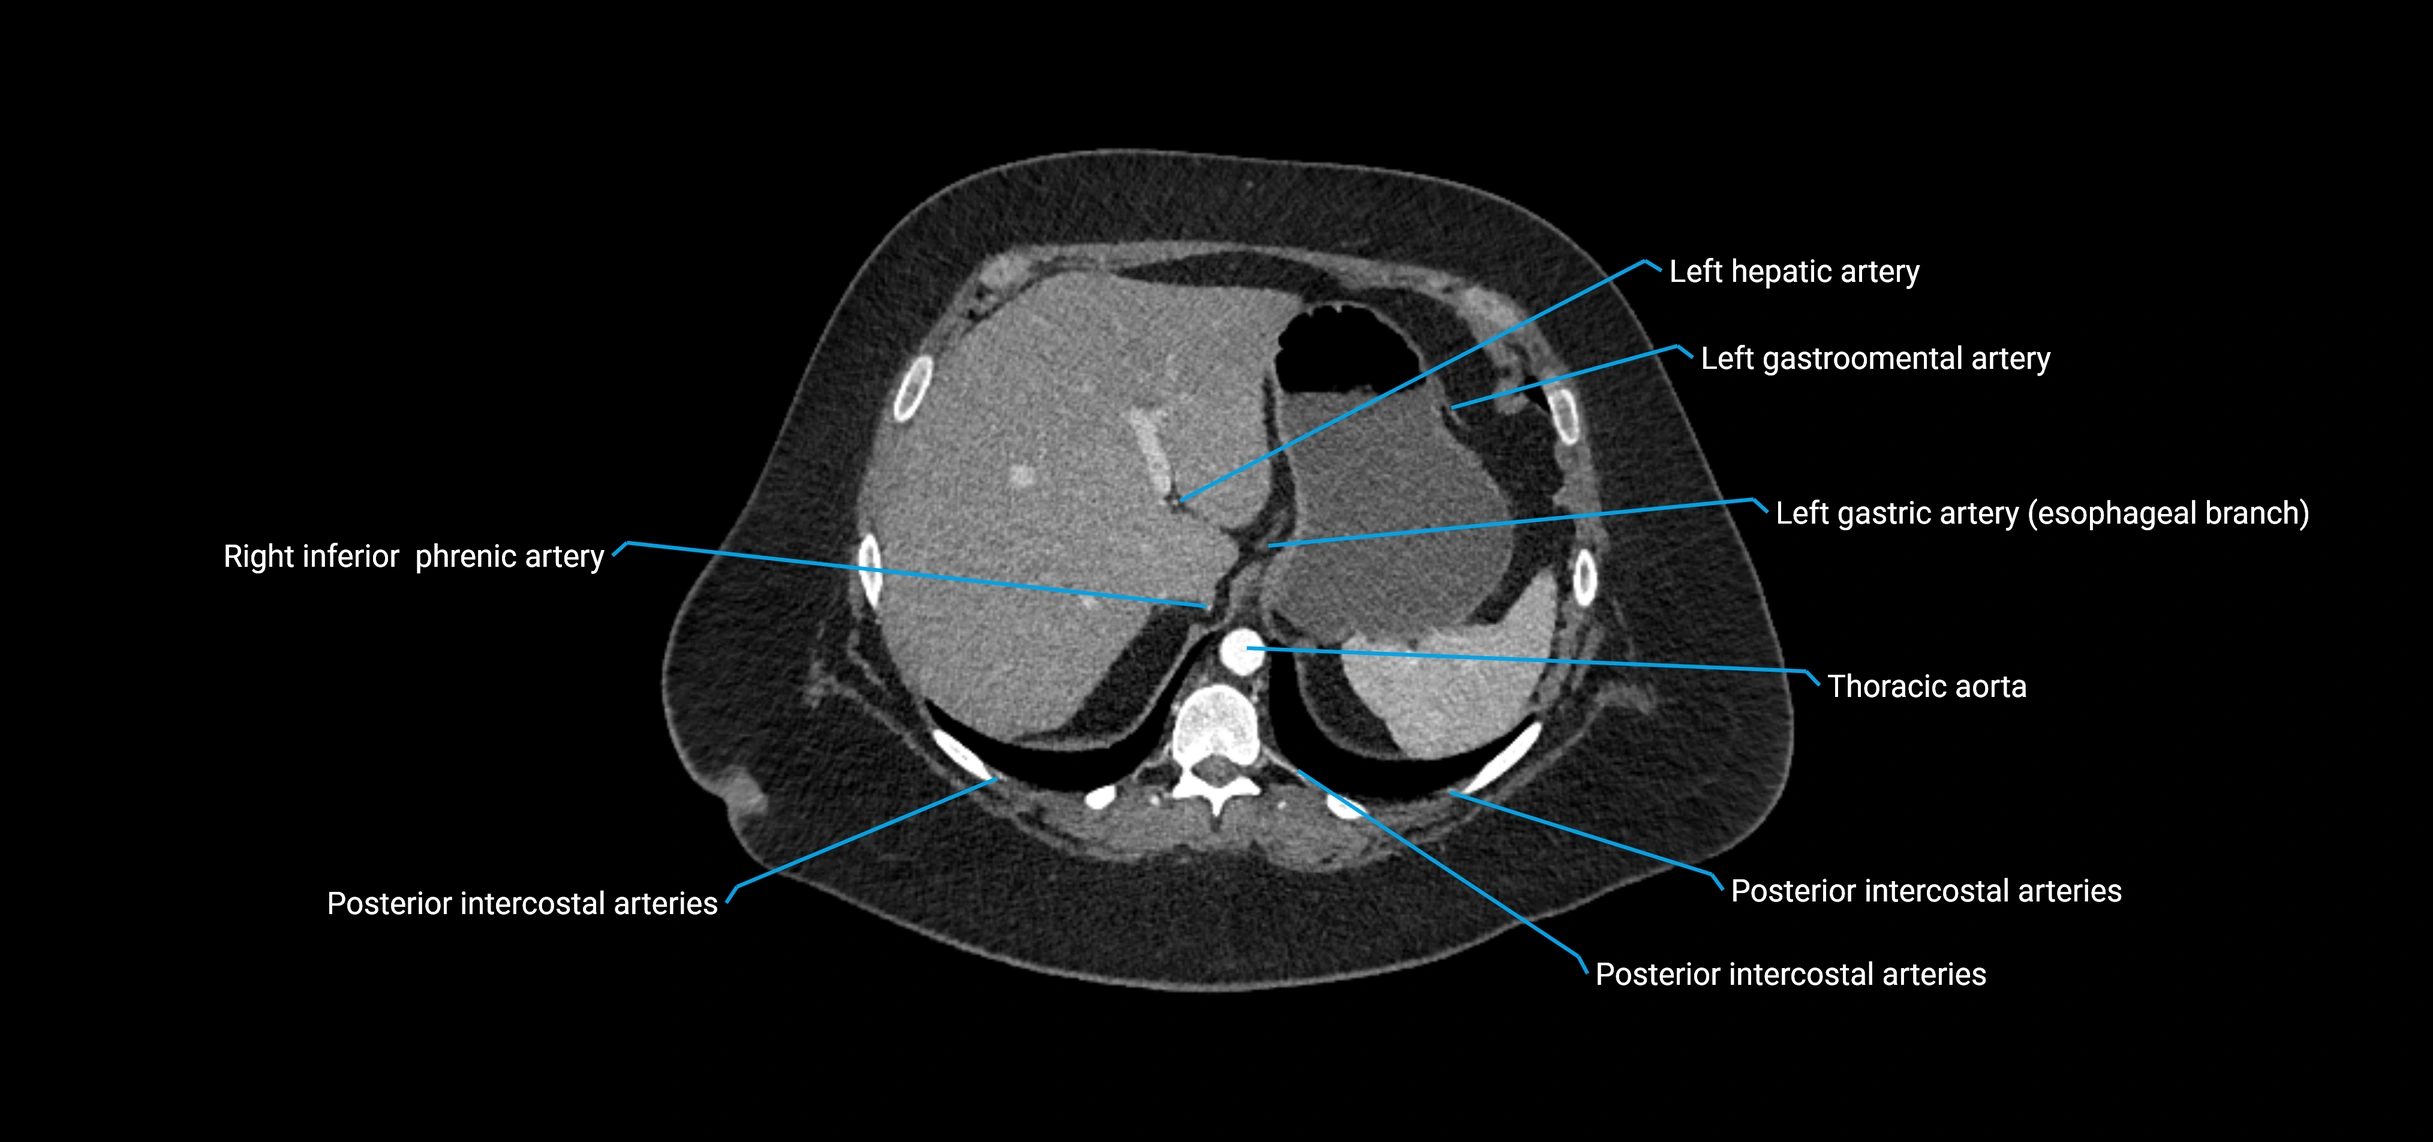

The abdominal aorta is the continuation of the thoracic aorta, beginning at the level of the aortic hiatus of the diaphragm (T12 vertebra) and terminating at the level of the L4 vertebra where it bifurcates into the right and left common iliac arteries. It lies slightly to the left of the midline and courses anterior to the vertebral bodies, surrounded by the retroperitoneal structures of the abdomen.

The abdominal aorta gives off numerous visceral and parietal branches, supplying the abdominal organs, pelvic structures, and lower limbs. It is the main conduit of oxygenated blood from the heart to the abdomen and lower body. The aorta is clinically significant as the common site of aneurysm, dissection, atherosclerosis, and traumatic injury.